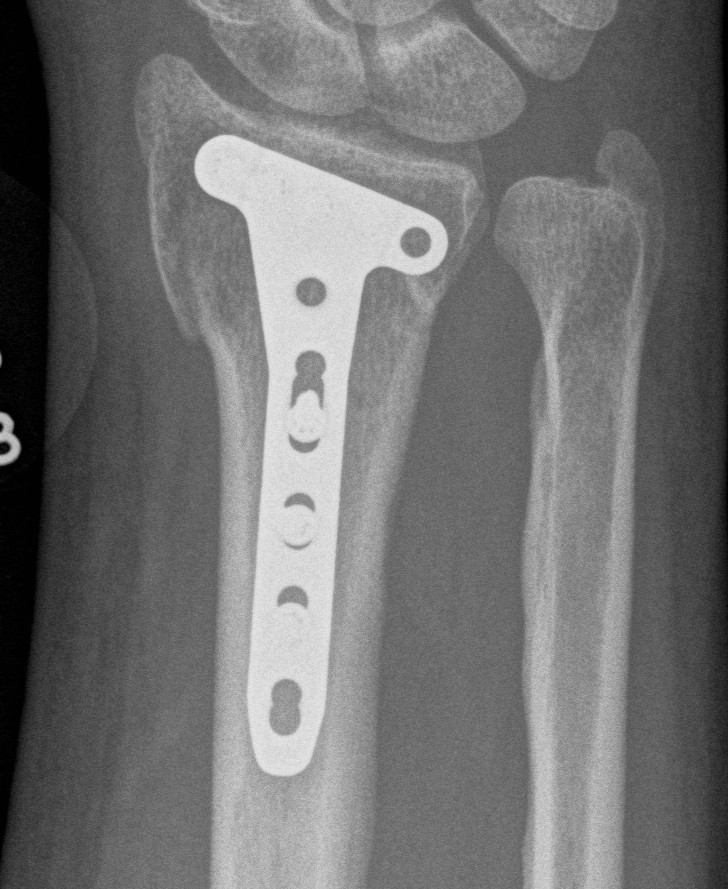

Surgical options

K wires

Volar locking plates

External fixation

Dorsal spanning plates

Distal Radius Fracture K wires APplateex fixbridge plate